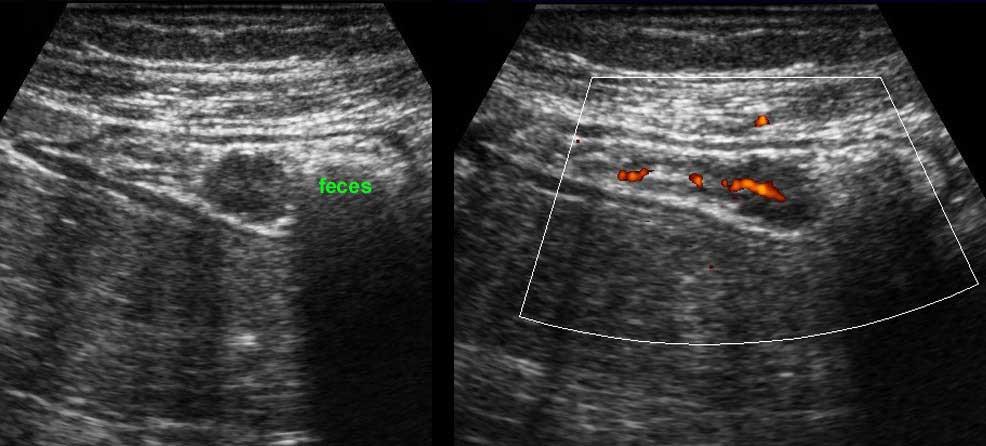

Nó không thể nhận diện riêng biệt khi hòa lẫn với phân tăng âm, như trong hình ảnh siêu âm đại tràng này.

Khi sử dụng đầu dò tần số cao, ba lớp giữa, bao gồm lớp niêm mạc sâu, lớp dưới niêm mạc và lớp cơ (đen-trắng-đen) luôn luôn hiển thị rõ ràng.

Ở bệnh nhân này với tình trạng ứ phân nặng, cấu trúc thành ba lớp chỉ có thể được nhận diện bằng đầu dò 12 MHz.

Ở bệnh nhân viêm loét đại tràng này, các mạch máu nổi bật (mũi tên) trong lớp dưới niêm mạc được hiển thị và xác nhận bằng Doppler màu ở hình bên phải.